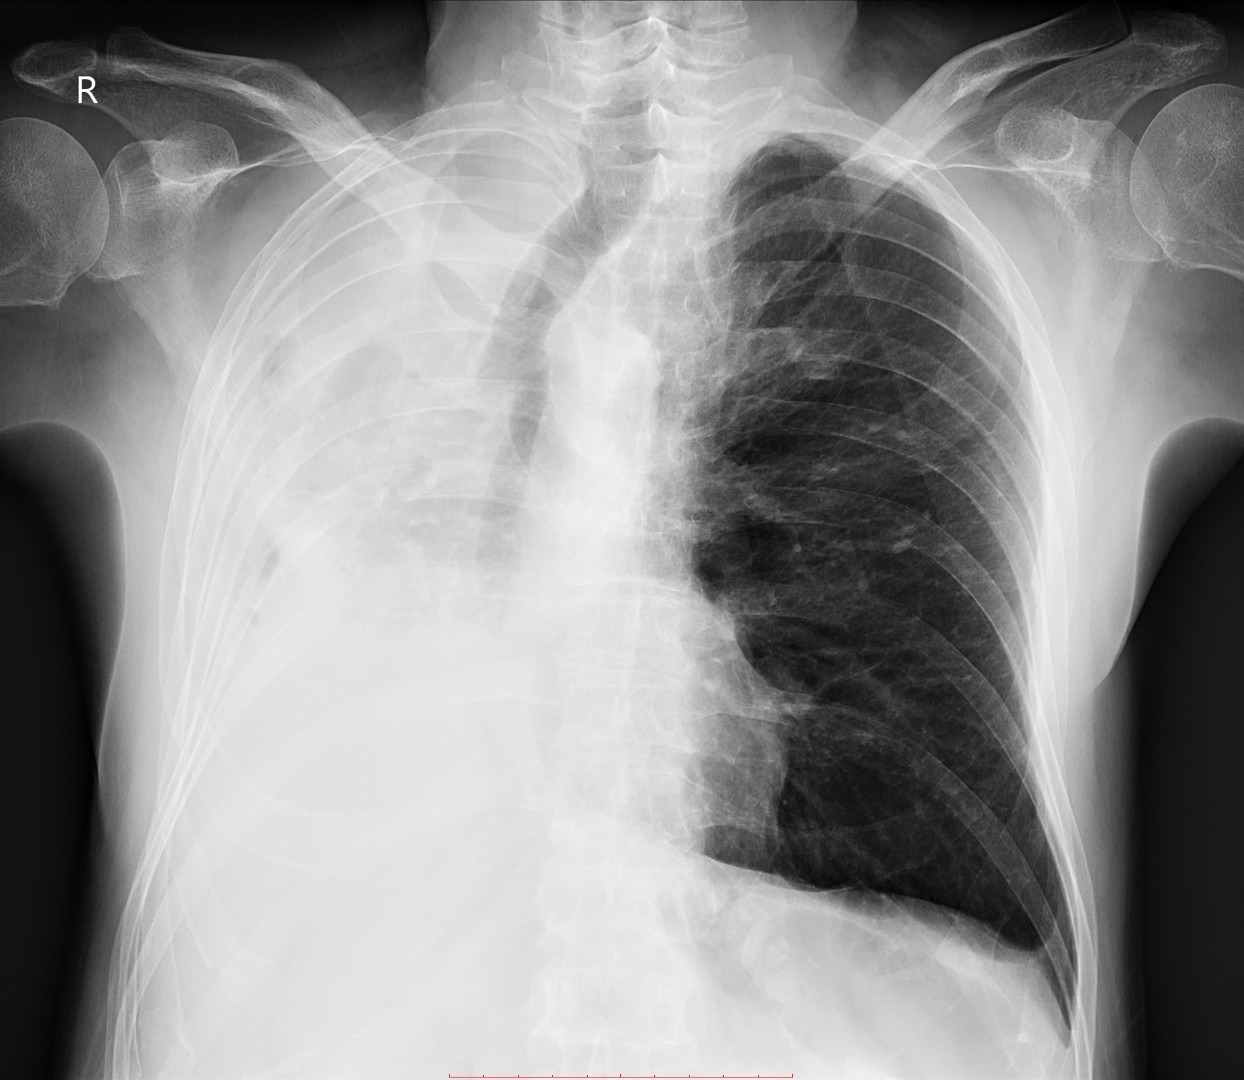

- გულმკერდის CXR 2 თვით ადრე.